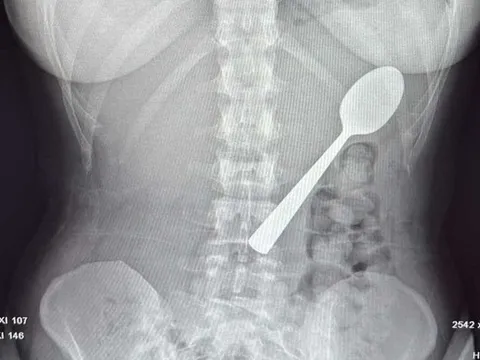

Bé trai 13 tuổi chảy máu nhiều, bác sĩ sốc khi phát hiện bí mật "đáng sợ" ở cổ - Ảnh 2.

Móc câu được loại bỏ, đảm bảo an toàn cho cháu bé.